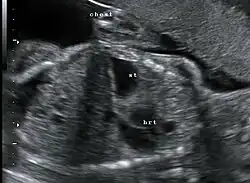

Ultraschallaufnahme einer Zwerchfellhernie

Die angeborene Zwerchfellhernie kann vor der Geburt im Ultraschall ab der 18. SSW dargestellt werden. Wird eine solche Diagnose vorgeburtlich gestellt, sollten weitere Untersuchungen (z. B. Kernspintomographie) in einem spezialisierten Zentrum erfolgen, um das Ausmaß an vorgeburtlicher Lungenschädigung einschätzen zu können, das die Prognose für das Überleben der Kinder und die angestrebte Erstversorgung wesentlich beeinflusst.